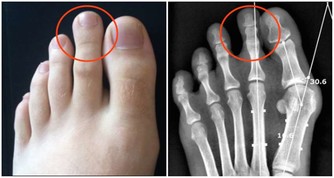

2年前,小羅右腳腳底突然長出一顆黑痣,一開始沒什麼感覺,但是隨著時間越長越大,到當地醫院檢查,醫生認為這是長雞眼,開了點藥膏給小羅。但塗了藥膏,黑痣絲毫不減消退,反而會凸起來,走路還硌腳,會痛。

於是,小羅又到市醫院檢查,結果最後確診為惡性黑色素瘤。

另外,長在手掌、腳底、腰部​周圍、腹股溝、腋下等部位的痣也會更危險,因為這些部位更容易被摩擦,在長期的刺激下痣容易發生破損、潰爛等,惡變的可能性也就更大。如果是這些部位的痣,建議及時到醫院切除。